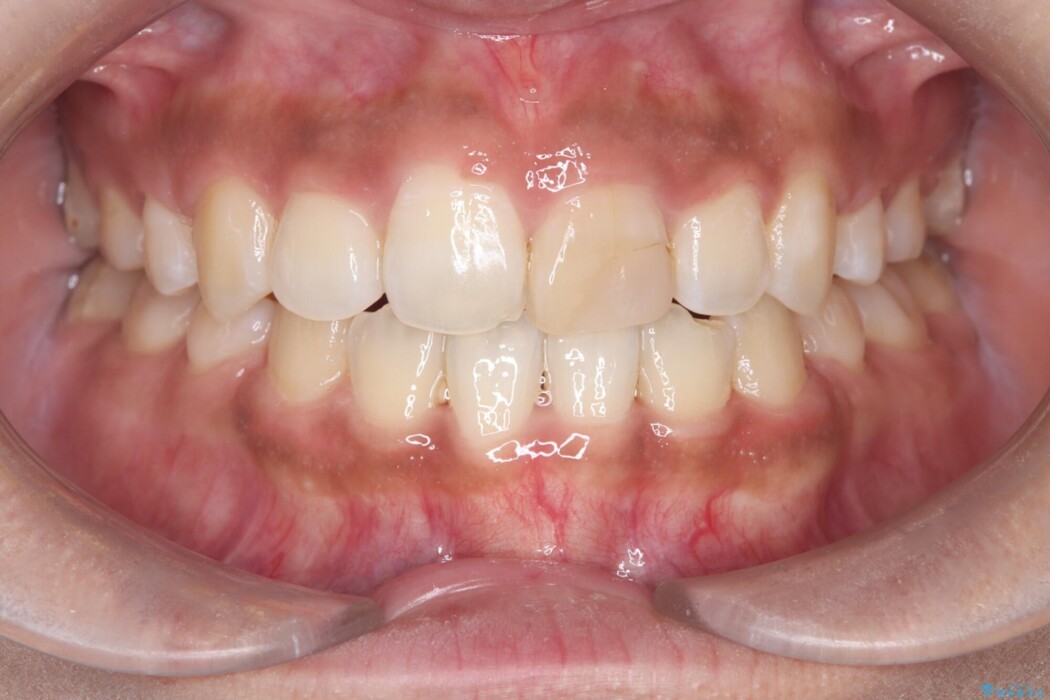

口元の突出感を改善し、横顔のラインを整えたいとご相談にいらっしゃった患者様です。

突出していた口元のボリュームを段階的に抑制し、理想的なバランスへと導きました。

機能面では上下の緊密な咬合を確立し、審美面ではEラインの劇的な改善を実現しました。 形態と機能の両立により、患者様の満足度が非常に高い仕上がりとなりました。